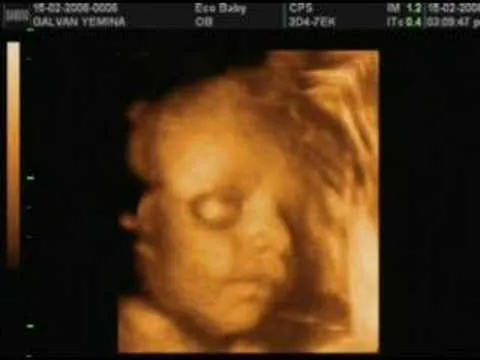

18 semanas eco en 3D,el sexo de mi bebé?!♥ Embarazo y mucho mas ...

Conoce las ECOgrafias 3D y 4D ~ el paciente y tú